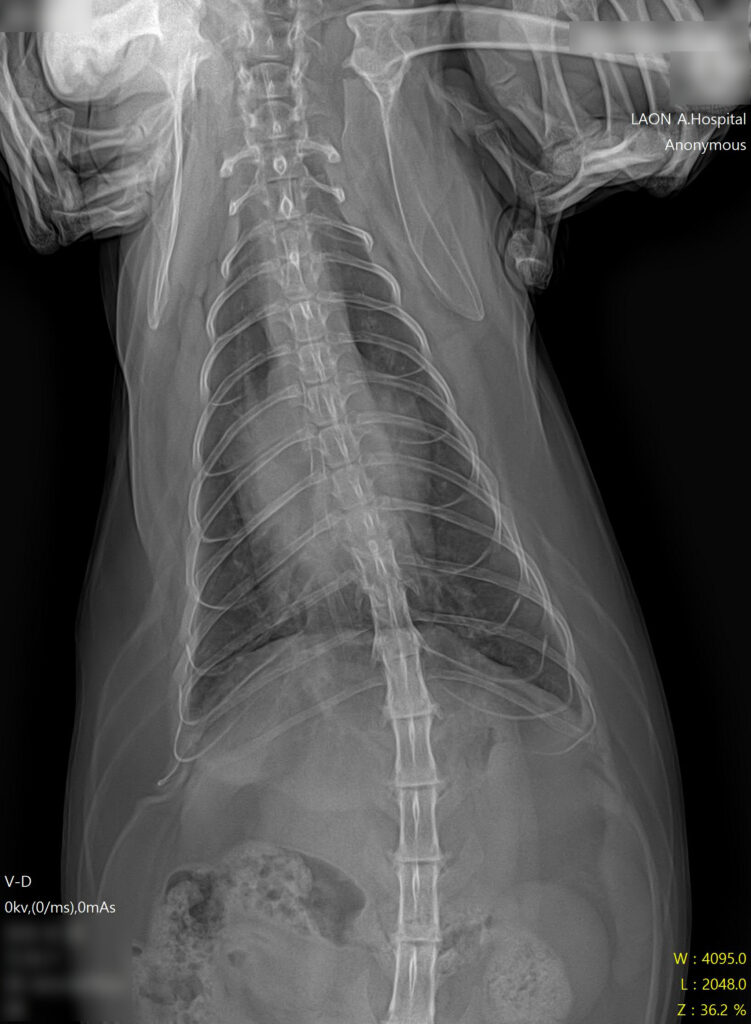

* 폐야가 하얗게 변한 폐수종 소견과 비대해진 심장 확인

- 방사선 검사: 흉부 방사선 촬영 결과, 폐 전반에 걸친 폐부종(pulmonary edema) 소견이 확인되었습니다. 또한 심장의 실루엣이 전형적인 ‘Valentine Shape(발렌타인 하트 모양)’으로 관찰되었는데, 이는 HCM(비대성 심근병증)에서 나타나는 특징적인 방사선 소견입니다.

* 폐수종 개선 및 깨끗해진 폐야 확인